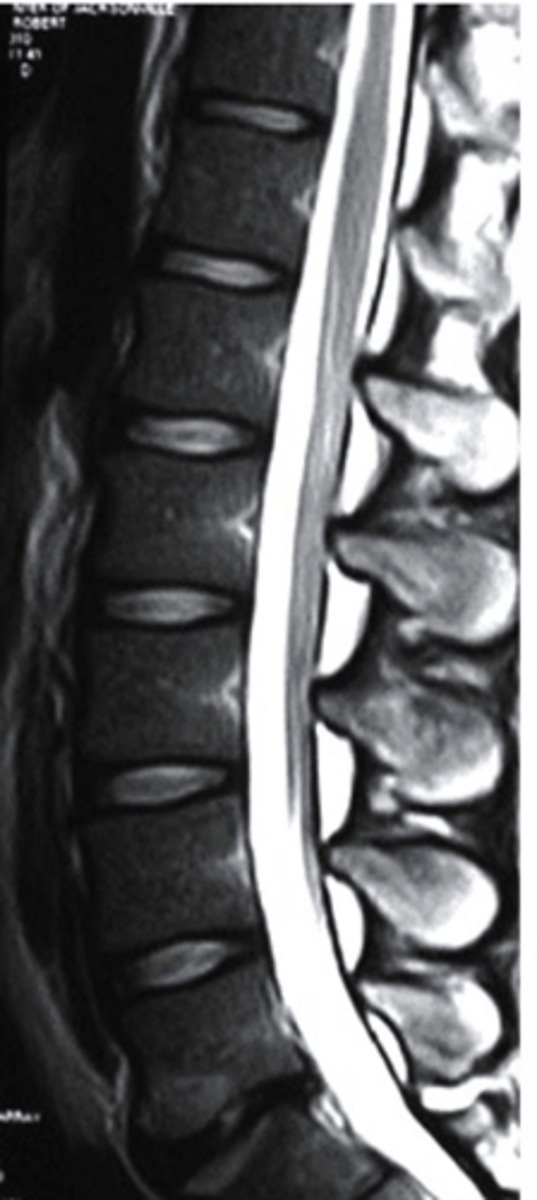

T2 MRI

what type of imaging is this?

a. T2 MRI

b. CT Scan

c. Radiograph

d. T1 MRI